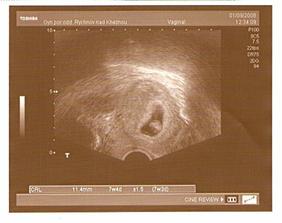

20.8.08 na utz je 2milimetrová prďolka

1.9.08 utz dopadl výborně, bije nám srdíčko a miminko má 11,4mm, odpovídáme 7tt+4